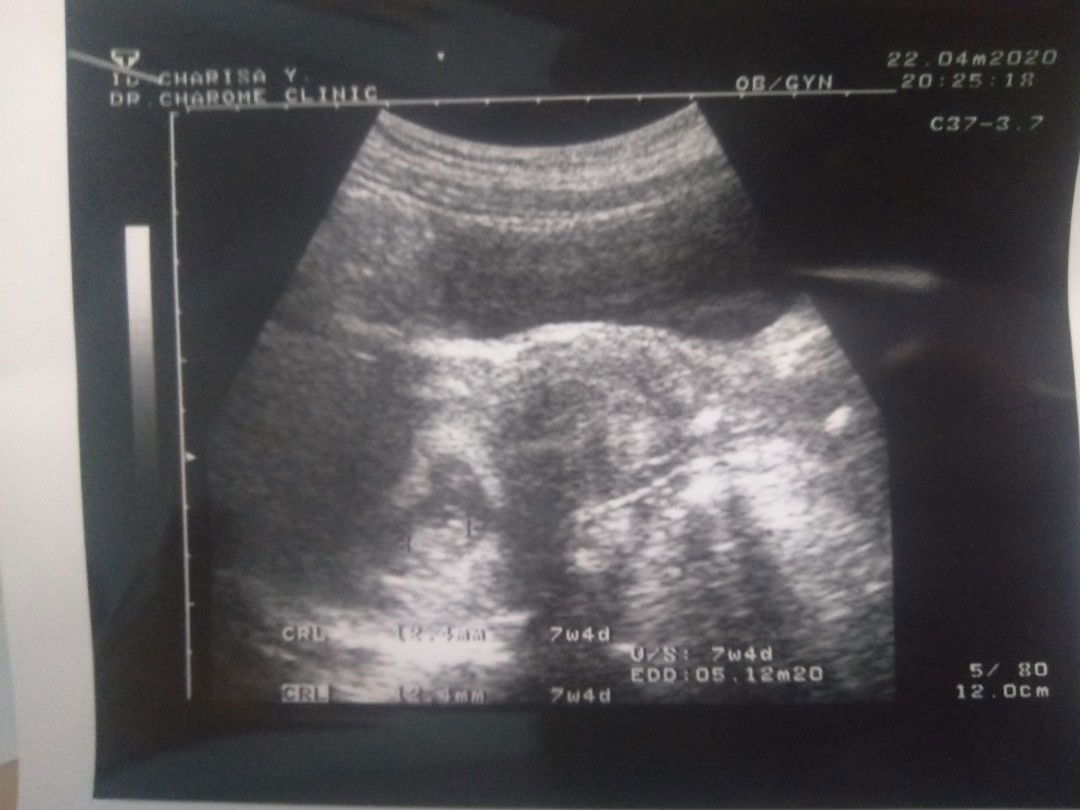

อายุครรภ์ในใบซาวด์ไม่ตรงกับที่นับตาม ประจำเดือน

วันที่ไปซาวด์เราอายุครรภ์ได้9สัปดาห์ แต่ในเครื่องซาวด์ระบุขนาดเด็กได้1เซนนิดๆระบุ ประมาณอายุครรภ์ได้7สัปดาห์4วัน อยากรู้ว่าเวลาคลอดมีใครคลอดตรงกับอันไหนค่ะ ประจำเดือนครั้งสุดท้ายวันที่ 16 กุมภาพันธ์